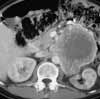

Figure 1

Abdominal CT with contrast demonstrates an 87 × 116-mm necrotic, partially enhancing mass in the region of the left adrenal gland (Figure 1). Chest CT with contrast reveals multiple bilateral noncalcified pulmonary nodules with no other apparent lesions in the thorax.